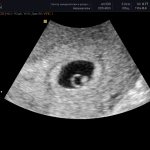

Leakage of amniotic fluid

In the second and third trimesters of pregnancy, a woman may notice light yellowish discharge - leaking amniotic fluid. Their appearance at the 40th week of pregnancy will “tell” that the baby will be born very soon. But such discharge in the second trimester may indicate the onset of premature labor. In both of these cases, especially in the second, you need to hurry to the doctor.

Toward the end of my pregnancy, my vaginal discharge increased. They began to resemble transparent mucus. I immediately thought that most likely it was amniotic fluid. My husband and I went to the maternity hospital, waited 4 hours - there were a lot of women in labor and whiners like me. After this, I was received by a very pleasant doctor, who examined me and briefly said that “the uterus is not ready,” but there was no leakage of water: according to the doctor, this is just a feature of the body, and such discharge is considered normal at the end of pregnancy. The doctor sent me home, which I was very happy about.